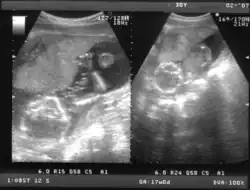

En cualquier momento del embarazo, en especial en presencia de un feto maduro en la segunda mitad del embarazo, es posible demostrar por ecografía transabdominal bidimensional o tridimensional tanto sus partes anatómicas como el saco vitelino.

Ecografía de 7 semanas -

Ecografía de 12 semanas -

Ecografía de 13 semanas -

Ecografía de 17 semanas -

Ecografía de 20 semanas